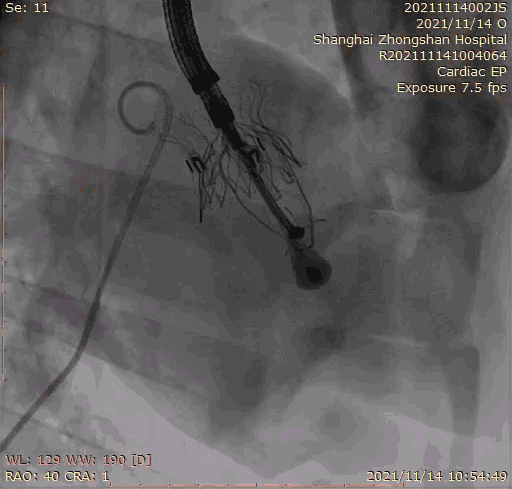

本次臨床前研究經(jīng)右側(cè)頸靜脈置入LuX-Valve Plus輸送系統(tǒng)可調(diào)彎鞘管,在DSA及超聲引導(dǎo)下將人工三尖瓣瓣膜植入到原有三尖瓣位置,利用獨(dú)特的錨定技術(shù)將人工瓣膜支架可靠固定在預(yù)定的位置。

Lux-Valve是全球第一款具有我國完全自主知識產(chǎn)權(quán)的經(jīng)導(dǎo)管介入三尖瓣置換系統(tǒng),利用前瓣夾持及室間隔錨定的復(fù)合方式進(jìn)行瓣膜裝置的固定,不依賴瓣環(huán)徑向支撐力,同時(shí)采用自適應(yīng)復(fù)合裙邊材料,有效的貼合密封柔軟的三尖瓣瓣環(huán),針對于三尖瓣返流的患者有優(yōu)異的療效。Lux-Valve Plus采用全新的經(jīng)血管輸送系統(tǒng),經(jīng)頸靜脈入路創(chuàng)傷更小,可以進(jìn)一步降低手術(shù)風(fēng)險(xiǎn)。相信在后期正式臨床研究開展中,Lux-Valve Plus必定會為更多的三尖瓣反流患者帶來福音。